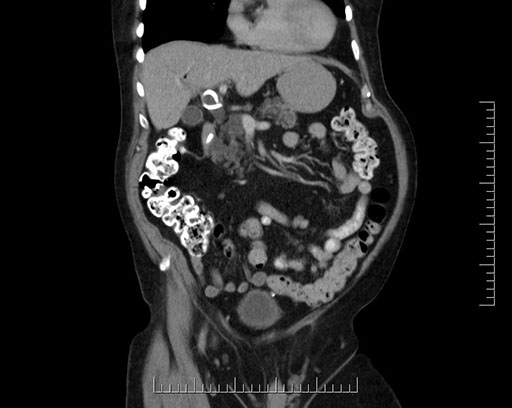

Imaging Analysis

Look through the patient's CT scan to identify any areas of concern for the necessary procedure.

Based on your CT findings, which issue(s) would give reason for "planned slowing down moment(s)" in this case?